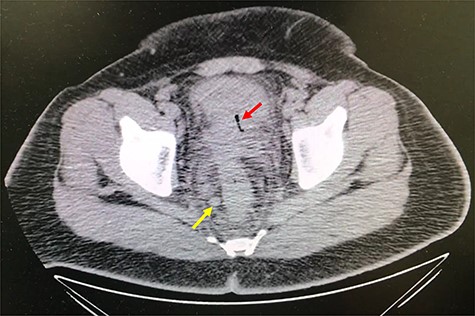

A 32-year-old man with no past medical or surgical history presented to the emergency department (ED) in April 2018, distressed and complaining of worsening pneumaturia for the past 3 days. The patient reported a 2-week history of polyuria, dysuria, suprapubic pain, tenesmus and inability to control his sphincters, prior to the ED-onset presentation. Further history revealed a 50-pound involuntary weight loss in a 5-month period, with partially treated urinary tract infections without resolution. He denied toxic habits, high-risk sexual behavior nor family history for colorectal cancer or inflammatory bowel disease. Based on the symptoms described, the rare triad of Gouverneur’s syndrome related to the EVF was considered. Physical evaluation revealed no palpable anorectal masses, adequate rectal tone and no visible gross blood. Urine analysis showed pyuria, hematuria, proteinuria with urine culture positive for Escherichia coli. Abdominopelvic computed tomography (CT) scan showed circumferential wall thickening of the rectum with surrounding fat stranding and numerous prominent pelvic lymph nodes (Fig. 1). Additionally, the scan showed pericolonic gas and fluid collection with a fistulous tract adjacent to the proximal rectum and the bladder (Fig. 2). In Figure 3, two hepatic hypodense lesions located in the right lobe of the liver were identified suggestive of metastasis. During colonoscopy, at approximately 20 cm from the anal verge a large, firm, irregular, friable, concentric mass was identified obstructing 95% of the lumen (Fig. 4). During surgery, the mass was not amenable for resection, due to its low pelvic location and size; a loop colostomy was performed for decompression, with liver tru-cut needle biopsy. Intraoperative cystoscopy was unsuccessful in placement of ureteral stents due to tumor invasion to the bladder.

Axial abdomen and pelvis CT scan showing hepatic hypodense lesion and possible liver metastasis (yellow arrow).